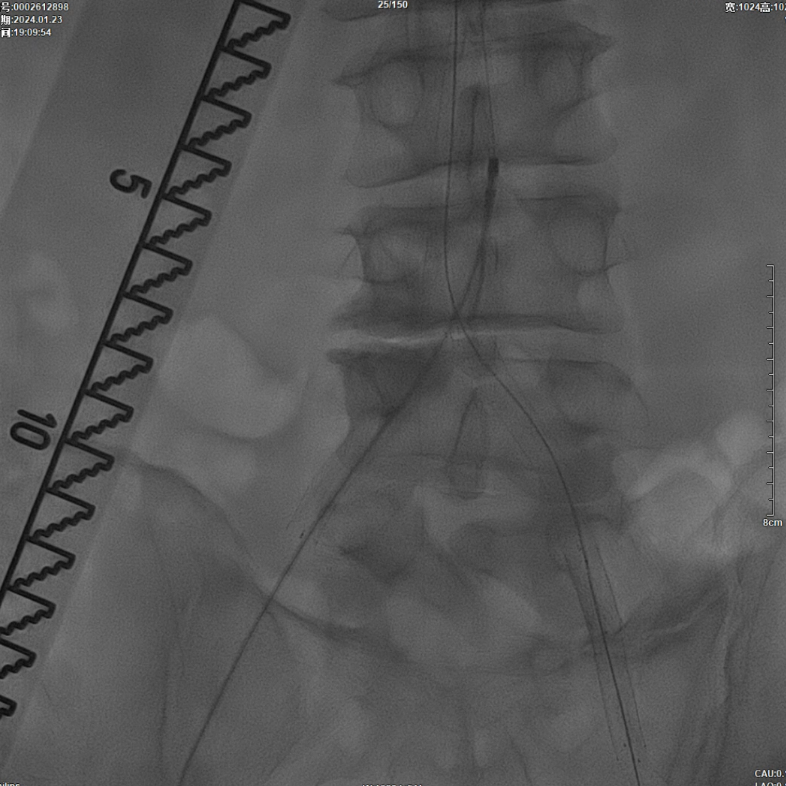

减容治疗

采用8F Rotarex导管对双侧髂动脉及腹主动脉下段进行减容处理。该器械对于陈旧性血栓具有良好的清除效果,且适用于支架内病变的治疗。减容治疗的主要目的在于获得理想的管腔空间,同时降低远端动脉栓塞的风险。